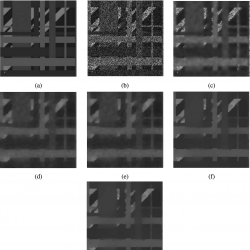

Fig. 5

Sample test images. (a) Cartoon-like image. (b) Real ultrasound image of a tumour. (c) Real ultrasound image of a fetus.

Fig. 6

Different methods of noise removal on a synthetic image. (a) Original image. (b) Image polluted by multiplicative speckle noise with Rayleigh distribution (variance is

$\upsilon =0.8$) (PSNR = 18.41, SSIM = 0.2372). (c) The denoising result using SRAD (Yu and Acton,

2002) (PSNR = 24.35, SSIM = 0.8551). (d) The result using VO method (Vese and Osher,

2003) (PSNR = 23.04, SSIM = 0.8044). (e) The denoised result using framelet regularization method without backward diffusion (Wang

et al.,

2014) (PSNR = 23.95, SSIM = 0.8164). (f) The denoised result using framelet regularization method and backward diffusion (Wang

2014) (PSNR = 24.23, SSIM = 0.8314). (g) The result of proposed method (PSNR = 27.24, SSIM = 0.9258).

In the first set, we have considered three images listed in Fig.

5 (one sample cartoon-like image and two real ultrasound images same as considered in Yu and Acton (

2002), Vese and Osher (

2003), Wang

et al. (

2014), and have compared the results of the proposed method with some related medical ultrasound despeckling techniques from the recent literature such as Yu and Acton (

2014). Firstly, we degraded a noise free sample cartoon-like image, (Fig.

5(a)), by multiplicative speckle noise with Rayleigh distribution by variance of

$\upsilon =0.8$ and then applied the proposed method on this image. To evaluate the efficiency of the proposed method, we used peak signal to noise ratio (PSNR) as a quantity to measure the quality of reconstruction of noisy images and SSIM as a structural similarity index between denoised image and original image. The despeckled image of our proposed method, (Fig.

6(g)), is compared with related techniques of Yu and Acton (

2014) with respect to PSNR and SSIM and are shown in Figs.

6(b)–

6(f). The measurements of PSNR and SSIM of the proposed method in comparison to those methods mentioned in Yu and Acton (

2014) show that the proposed approach is better than those methods, in addition, the proposed method preserves the texture and edges of images while the methods of Yu and Acton (

2014) lead to smooth edges of images. Also, to evaluate the visual quality of the proposed approach, similarly to the methods mentioned in Yu and Acton (